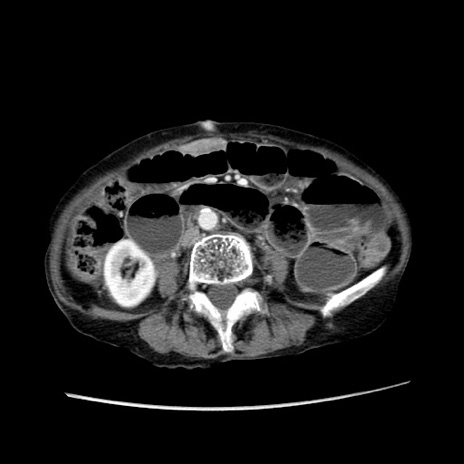

症例25(横断像)

【症例】80歳代女性

【主訴】胸のつかえ感

【現病歴】約9時間前に食後から胸のつかえた感じあり、嘔吐あり、来院。

【既往歴】胃癌(全摘)、胆摘、虫垂炎

【身体所見】心窩部に圧痛あり、反跳痛なし。

【データ】WBC 5700、CRP 0.05